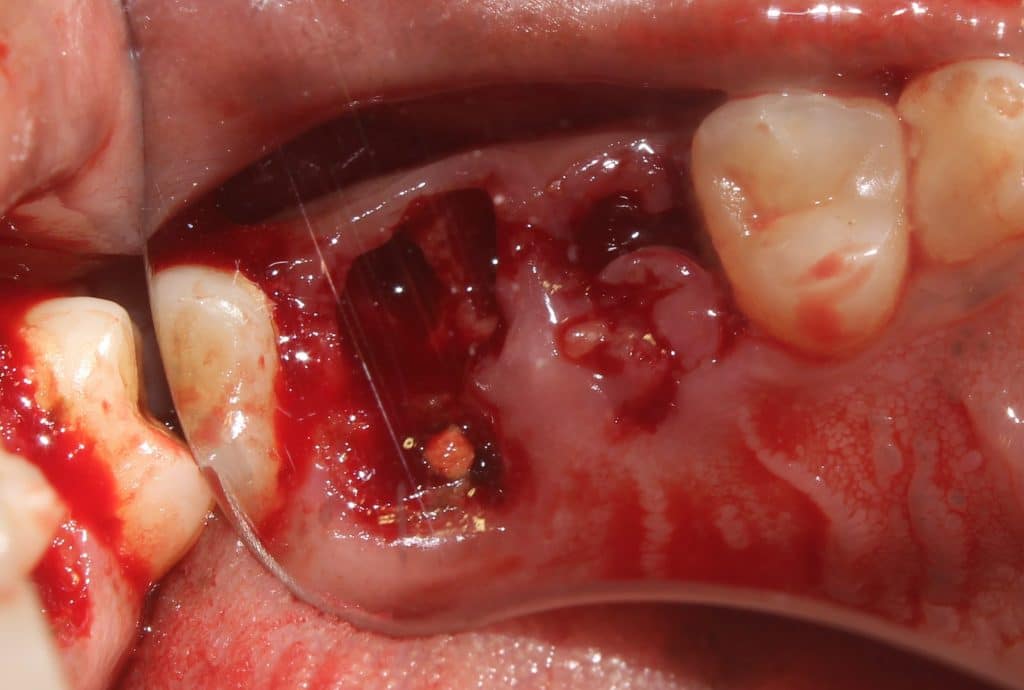

Initial presentation of broken down teeth.. previously root treated..

the premolar is elevated from the mesial purchase point.. and removed..